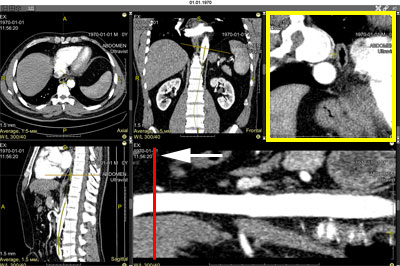

Displays, in addition to the resulting cMPR, orthogonal (cross-sectional) slices perpendicular to the construction curve

To show orthogonal slices, click the button in the cMPR series header

An orthogonal projection panel will be added to the screen

A red linear cursor for controlling orthogonal slice scrolling will appear on the cMPR

Moving (hover mouse cursor, press and hold left mouse button, move mouse) the linear cursor on the cMPR leads to synchronous scrolling of orthogonal slices

Scrolling orthogonal slices synchronously moves the linear cursor on the resulting cMPR